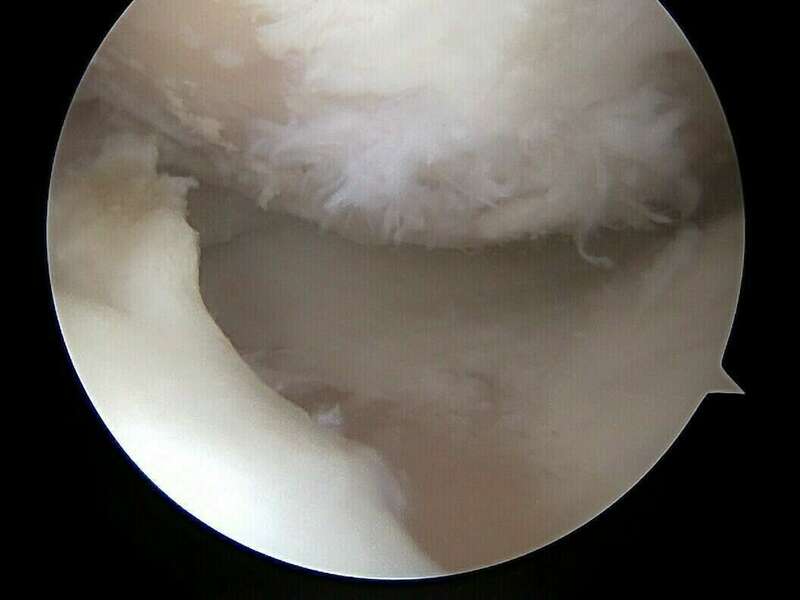

La ménisectomie sous arthroscopie vise à réséquer une lésion méniscale symptomatique tout en conservant un maximum de ménisque sain. L'arthroscopie permet d’explorer l'intérieur du genou, de faire un diagnostic et de traiter des lésions, en particulier méniscales et ligamentaires.

L'Arthroscope est un tube de quelques millimètres de diamètre, muni d'un système optique et d’un système d'éclairage, il est couplé à une caméra vidéo miniaturisée, elle-même reliée à un écran de télévision couleur. Il est mis en place à l'intérieur du genou par un orifice minime, un ou parfois plusieurs autres petits orifices cutanés sont nécessaires pour l'introduction d'instruments fins dans l'articulation. Pendant tout l'examen, le genou est gonflé avec du liquide (sérum physiologique).

L'arthroscopie permet de regarder : la cavité articulaire, les ménisques (interne et externe), le cartilage (de la rotule, du fémur, du tibia), la membrane synoviale (poche qui entoure l’articulation), et les ligaments croisés. Elle permet de réaliser une cartographie lésionnelle de votre genou.

De grandes avancées technologiques ont vu le jour ces-dernières années. L'utilisation d’instruments miniaturisés de haute précision permet désormais d’effectuer des méniscectomies « a minima » pour conserver un maximum de ménisque sain.

Album photo